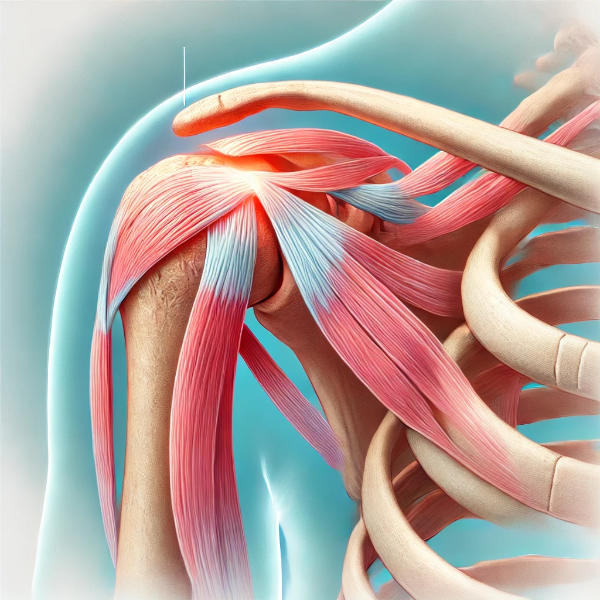

회전근개파열은 어깨의 네 개의 근육과 힘줄로 구성된 회전근개(rotator cuff)가 손상된 상태를 말합니다. 이 회전근개는 어깨 관절을 안정화하고 팔을 들어 올리거나 회전하는 데 필수적인 역할을 합니다. 특히, 어깨는 전신에서 가장 가동 범위가 넓은 관절 중 하나로, 일상적인 동작부터 스포츠 활동까지 많은 움직임을 수용해야 하기 때문에 쉽게 손상될 수 있습니다. 회전근개파열은 이러한 어깨 기능을 저해하는 주요 요인으로 작용하며, 심한 경우 일상적인 생활에도 큰 불편을 초래할 수 있습니다.

회전근개파열의 원인

회전근개파열은 나이와 활동량, 외상 등 다양한 요인에 의해 발생할 수 있으며, 주요 원인은 다음과 같습니다.

퇴행성 변화

- 나이와 관련된 퇴행성 변화는 회전근개파열의 주된 원인 중 하나입니다. 나이가 들수록 어깨 근육과 힘줄이 약해지고, 미세한 손상이 축적됩니다.

- 퇴행성 변화는 주로 50대 이상의 연령층에서 자주 나타나며, 세포 재생 능력의 저하로 인해 근육과 힘줄이 자연스럽게 약해집니다.

- 반복적인 사용에 의해 회전근개가 마모되며, 이 과정에서 힘줄이 점진적으로 약해지다가 결국 파열이 일어납니다.